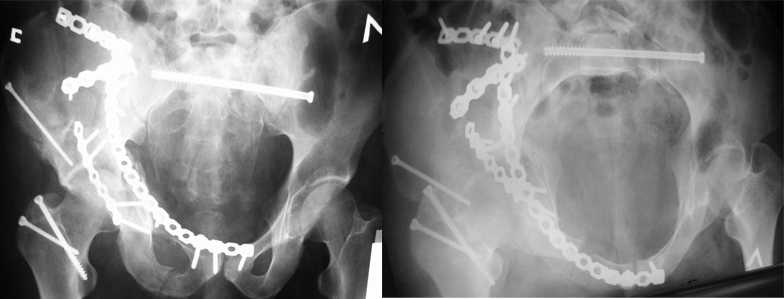

В положении на спине подвздошным и надлобковым доступом восстанавливается тазовое кольцо, фиксация пластинами. При хорошей репозиции может улучшиться конгруэнтность в суставе.

Затем, если положение хорошее, закрытый остеосинтез шейки винтами.

Если нет - в положении на боку, синтез задней колонны из наружно-латерального доступа и синтез головки винтами, но уже под визуальным контролем.

На картинке подобный случай, только без шейки, сделано через месяц или полтора после травмы.